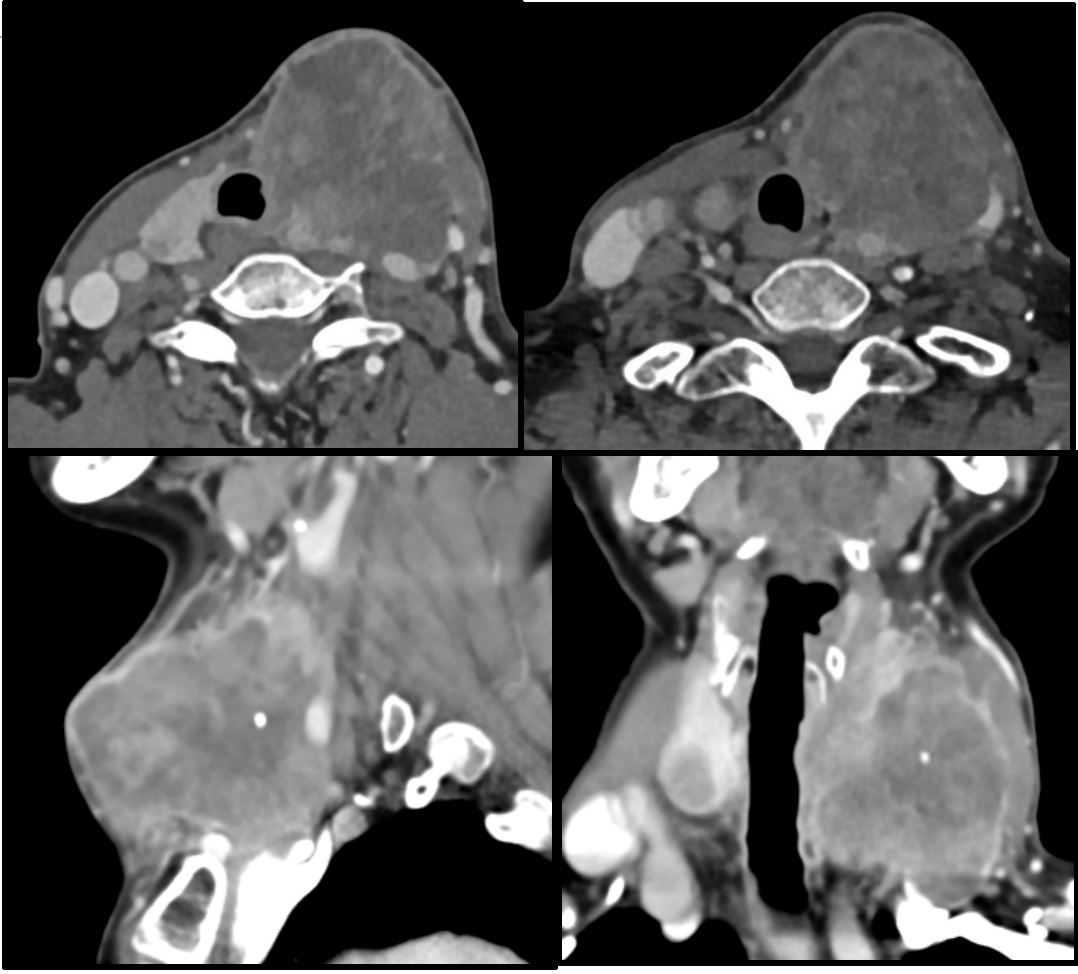

甲状腺癌患者在经过规范治疗后,有活40年的可能甲状腺癌的预后情况与其病理类型密切相关分化型甲状腺癌如乳头状癌和滤泡状癌的恶性程度较低,生物学行为相对温和即使出现颈部淋巴结转移或远处转移,通过规范的手术放射性碘治疗以及...